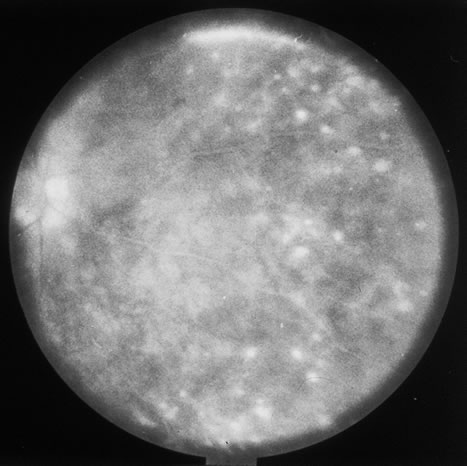

In primary ocular HSV infections, a severe follicular conjunctivitis with regional adenopathy is present. Vesicles may appear on the eyelid skin or lid margin, producing blepharitis (Fig. 3). Corneal involvement initially takes the form of a superficial punctate keratitis, which may progress to dendritic or geographic ulceration. Stromal infiltrates and uveitis are less common and relatively mild in primary disease. In uncomplicated cases, lesions usually heal completely in 2 to 3 weeks without scarring. Most cases of ocular HSV are recurrences. Recrudescent ocular herpes may take the form of dendritic or geographic ulcers, recurrent erosions, interstitial or disciform stromal keratitis, and anterior uveitis.3 HSV may also be an agent of retinitis and acute retinal necrosis (Fig. 4).

The acute retinal necrosis (ARN) syndrome is most often caused by the herpes zoster virus, although occasionally it may be a result of herpes simplex infection.12 It is typically described in healthy patients although association with immunosuppressed patients has also been described. Granular, nonhemorrhagic areas of retinal necrosis may be observed in the fundus, often rapidly coalescing with resulting blindness often caused by retinal detachment. There is often an associated vasculitis and vitritis. In immunocompromised patients VZV or HSV retinitis may also take the pattern of progressive outer retinal necrosis (PORN) (Fig. 6). PORN differs from ARN in that the former is multifocal, localized to the outer retina, and is less often associated with vasculitis and vitritis.